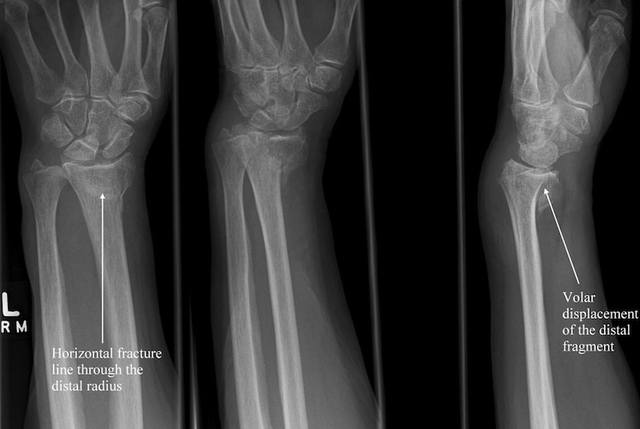

<br /><br />3) Barton: перелом описан в двух вариантах - волярном и дозальном и является частным случаем описанных выше переломов Смита либо Коллеса. Отличие - подвывих в лучезапястном суставе.<br /><br />Волярный Barton:<br /><br />

<br /><br />Тыльный Barton:<br /><br />

<br /><br /><br />4) Hutchinson - внутрисуставной перелом шиловидного отростка лучевой кости.<br /><br />